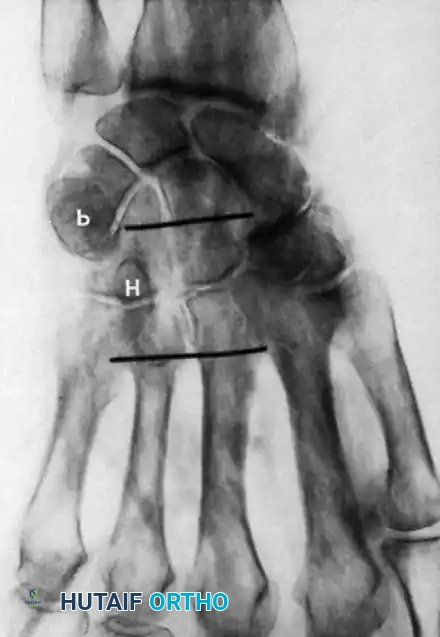

Anatomy and Biomechanics of the Carpal Tunnel

The carpal tunnel is a rigid, cylindrical, and highly inelastic fibro-osseous canal connecting the volar forearm to the mid-palm. Its precise anatomical confines are critical to understanding the pathophysiology of median nerve compression and the rationale for surgical decompression.

- Dorsal Boundary (Floor): Formed by the concave transverse arch of the carpal bones, specifically the scaphoid, trapezium, trapezoid, capitate, hamate, triquetrum, and pisiform, stabilized by robust intrinsic carpal ligaments.

- Medial Boundary (Ulnar): Composed of the hook of the hamate, the triquetrum, and the pisiform.

- Lateral Boundary (Radial): Defined by the scaphoid tuberosity, the crest of the trapezium, and the fibro-osseous sheath enclosing the flexor carpi radialis (FCR) tendon.

- Ventral Boundary (Palmar Roof): Primarily constituted by the flexor retinaculum. This complex structure includes the deep investing fascia of the forearm proximally, the thick transverse carpal ligament (TCL) over the radiocarpal joint, and the distal aponeurosis between the thenar and hypothenar musculature.

Figure 1: Anatomical representation of the median nerve and flexor tendons within the carpal tunnel.

Within this tightly confined space, the median nerve is the most ventral (superficial/palmar) structure, rendering it highly susceptible to extrinsic compression. Dorsal (deep) to the median nerve lie the nine flexor tendons: four flexor digitorum superficialis (FDS), four flexor digitorum profundus (FDP), and the flexor pollicis longus (FPL).